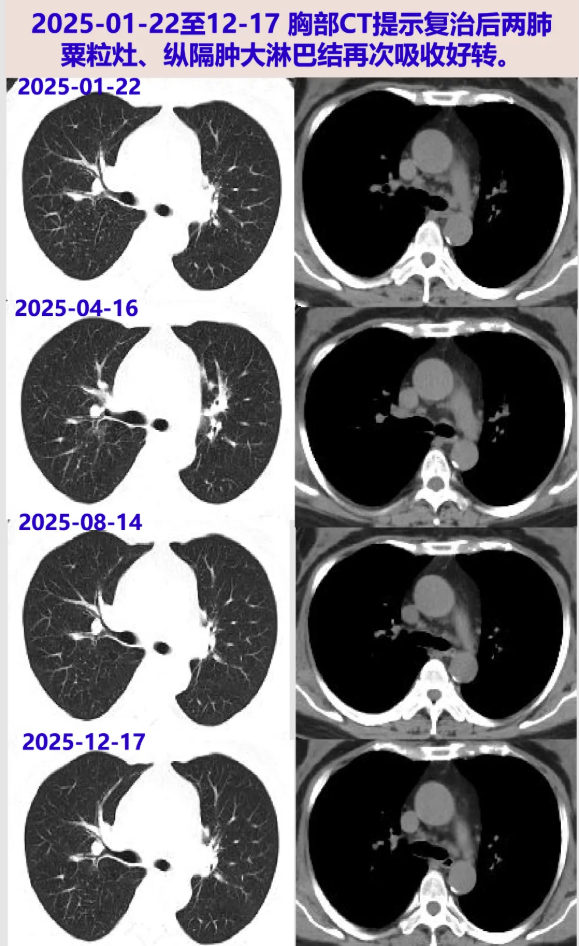

2024-12-09 胸部CT:纵隔及肺门多发淋巴结肿大,两肺多发病变,均较09-04片进展;ACE阴性。考虑结节病复发,再次启动糖皮质激素治疗,方案:甲泼尼龙32mg qd×1周、28mg qd×2周、24mg qd维持。

2025-01-22 胸部CT:较24-12-09片肺内病灶吸收,纵隔淋巴结缩小。激素减量方案:甲泼尼龙20mg qd×3周、16mg qd维持。

2025-04-16 胸部CT:较前片好转(最大淋巴结位于左下气管旁19×14mm);炎症指标、ACE阴性;目前甲泼尼龙16mg qd,后续减量方案:14mg qd×2月、12mg qd×2月。

2025-08-14 胸部CT:较前片相仿。后续减量方案:10mg qd×2月、8mg qd×2月。

2025-12-17 胸部CT:较前片相仿。继续甲泼尼龙8mg qd,2~3月后复查胸部CT。